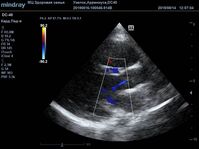

Найти их очень просто, достаточно сечений LAXLV (длинная ось) и SAXBASE (короткая ось). Специфические крупные шаровидные структуры – узелки Аррениуса - на кончиках полулуний клапана обнаружил ультразвуковой прибор

Mindray DC-40. В цветовом допплере без труда определяется аортальная регургитация легкой степени. Оценить её можно в CFM по соотношению JW/LVOT.